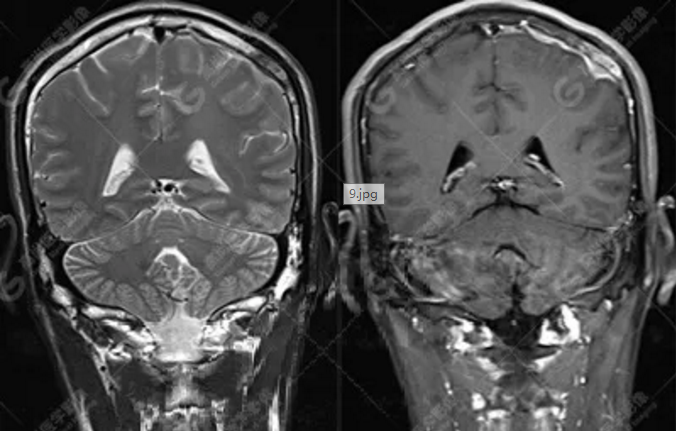

中年男性,反復(fù)出現(xiàn)手腳抽搐、暈倒伴意識(shí)喪失3年余,臨床擬診癲癇發(fā)作,后到高尚醫(yī)學(xué)影像診斷中心行MR檢查。

MR圖像

MR診斷

左側(cè)額頂部顱骨骨質(zhì)破壞并相鄰硬腦膜增厚強(qiáng)化,考慮Rosai Dorfman病(RDD)可能,需與朗格漢斯細(xì)胞組織細(xì)胞增生癥鑒別。

左側(cè)額頂部病灶符合Rosai Dorfman病。